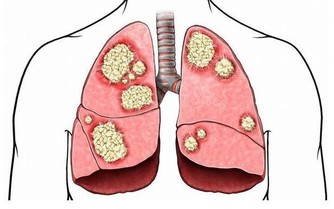

習慣性便秘因用力增加腹壓,屏氣使勁排便或誘發中老年男性高血脂、心腦血管病、動脈硬化、腫瘤等疾病及其併發症的罪魁禍首,導致老人心腦血管病變死亡率急劇增加,出現痔瘡、肛裂等問題,令人痛苦不堪。